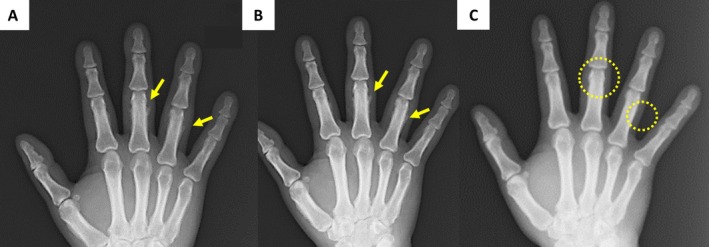

Hypertrophic pulmonary osteoarthropathy is a rare paraneoplastic syndrome affecting < 1% of patients with non-small cell lung cancer, characterized by clubbed fingers, periosteal proliferation, and arthritis. Although symptoms improve after treatment, objective functional recovery has not previously been reported. We present a 52-year-old male heavy smoker with right upper lobe adenocarcinoma and hypertrophic pulmonary osteoarthropathy causing profound grip strength impairment (5/2 right/left kilogram-force (kgf)). Genetic testing identified the KRAS G12C mutation. The patient underwent right upper lobectomy after which his arthralgia resolved immediately and grip strength recovered progressively (16/12 kgf, postoperative day 3; 40.9/32.9 kgf, 3 months), reaching normal adult levels. Periosteal changes initially persisted but resolved by 1 year. This case provides the first objective documentation of functional recovery in a patient with hypertrophic pulmonary osteoarthropathy, suggesting that impaired grip strength may be caused by joint inflammation and edema affecting bone-tendon attachments, rather than by muscle weakness alone. The KRAS G12C mutation may contribute to the development of hypertrophic pulmonary osteoarthropathy through upregulation of vascular endothelial growth factor via the Raf pathway. This case provides valuable insights into the pathophysiology of hypertrophic pulmonary osteoarthropathy and confirms that functional impairment is reversible with appropriate treatment.